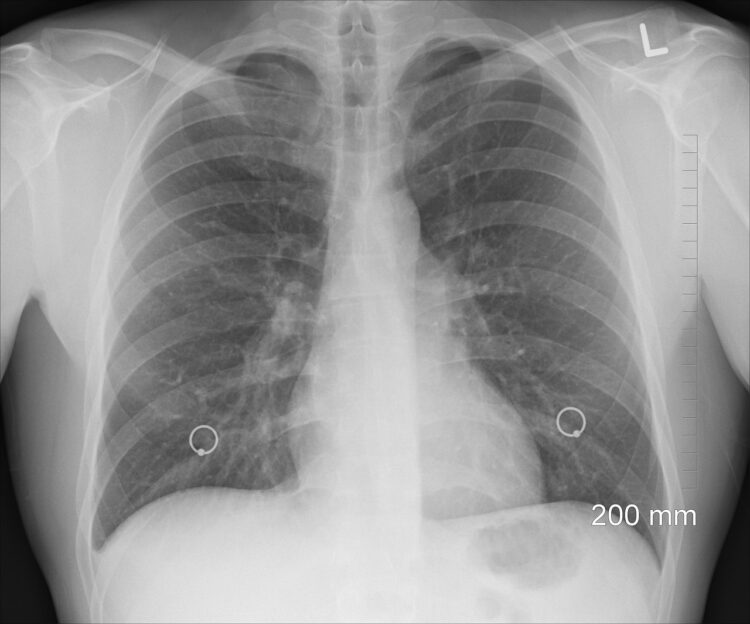

fot. Pixabay